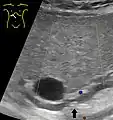

Abdominal ultrasonography of a common bile duct stone